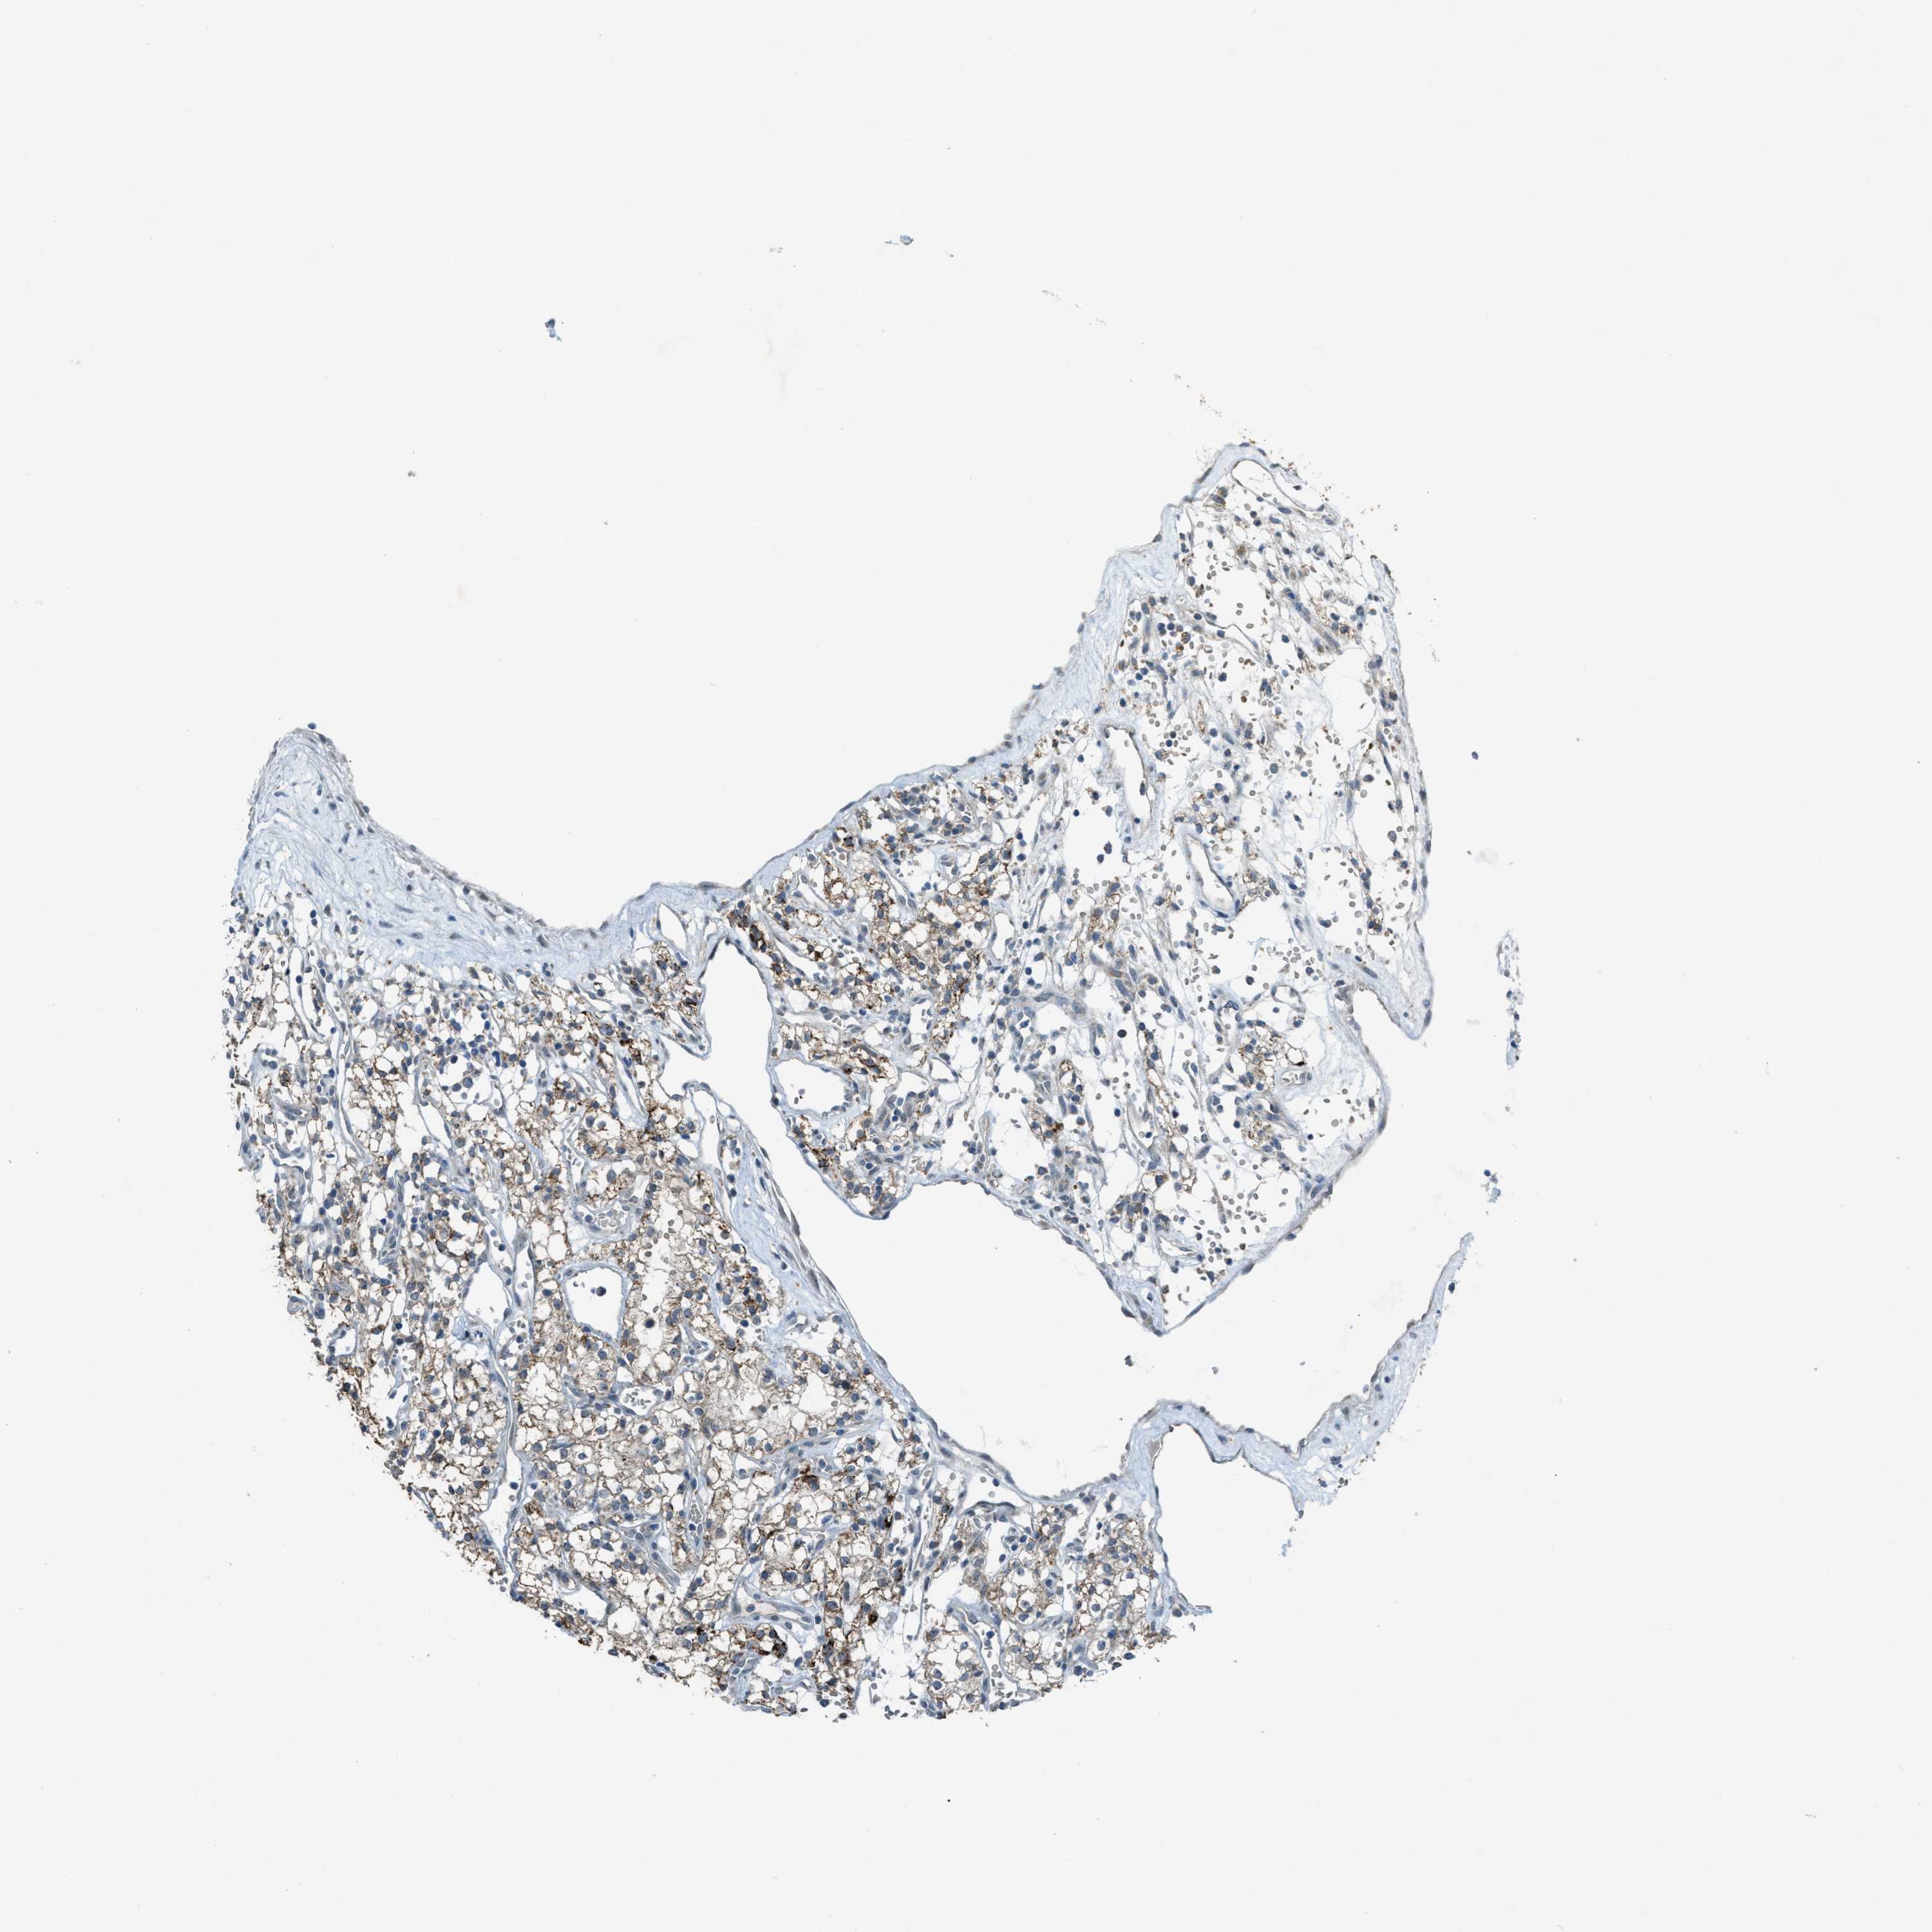

KIDNEY RENAL CLEAR CELL CARCINOMA (VALIDATION) - Interactive survival scatter ploti

The Survival Scatter plot shows the clinical status (i.e. dead or alive) for all individuals in the patient cohort, based on the same data that underlies the corresponding Kaplan-Meier plots. Patients that are alive at last time for follow-up are shown in blue and patients who have died during the study are shown in red.

The x-axis shows the expression levels (FPKM) of the investigated gene in the tumor tissue at the time of diagnosis. The y-axis shows the follow-up time after diagnosis (years). Both axes are complimented with kernel density curves demonstrating the data density over the axes. The top density plot shows the expression levels (FPKM) distribution among dead (red) and alive patients (blue). The right density plot shows the data density of the survived years of dead patients with high and low expression levels respectively, stratified using the cutoff indicated by the vertical dashed line through the Survival Scatter plot. This cutoff is automatically defined based on the FPKM cutoff that minimizes the p-score. The cutoff can be changed by dragging the vertical line or by entering a cutoff value in the square labeled "Current cut-off".

Under the Survival Scatter plot the p-score landscape (black curve; left axis) is shown together with dead median separation (red curve; right axis). Dead median separation is the difference in median mRNA expression between patients who have died with high and low expression, respectively. It is calculated as follows: median FPKM expression of dead patients with high expression - median FPKM expression of dead patients with low expression. This is intended to aid the user in visually exploring custom cutoffs and the associated p-scores and dead median separation.

Individual patient data is displayed and can be filtered by clicking on one or more of the category buttons on the top of the page. Categories describing expression level and patient information include: high, low, alive, dead, female, male and tumor stages. The scale of the x-axis can be toggled between linear and log-scale by clicking on the "x log" button. Mouse-over function shows TCGA ID, patient information and mRNA expression (FPKM) for each patient.

& Survival analysisi

Kaplan-Meier plots summarize results from analysis of correlation between mRNA expression level and patient survival. Patients were divided based on level of expression into one of the two groups "low" (under cut off) or "high" (over cut off). X-axis shows time for survival (years) and y-axis shows the probability of survival, where 1.0 corresponds to 100 percent.

CDON is not prognostic in Kidney Renal Clear Cell Carcinoma (validation)

Best expression cut offi

Based on the FPKM value of each gene, patients were classified into two groups and association between prognosis (survival) and gene expression (FPKM) was examined. The best expression cut-off refers the FPKM value that yields maximal difference with regard to survival between the two groups at the lowest log-rank P-value. Best expression cut-off was selected based on survival analysis .

: 6.36

Average pTPM 5.1

Number of samples 100